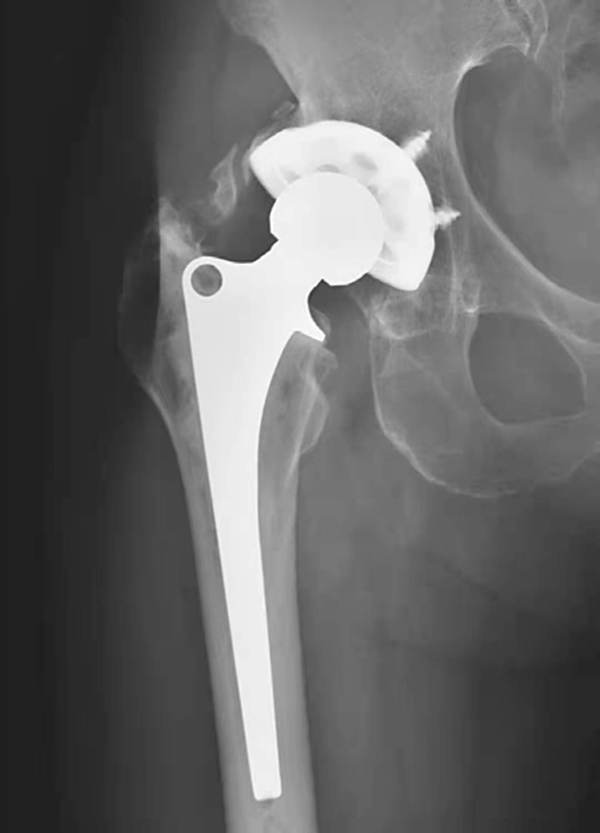

图3 无菌性松动

平片,示右侧髋臼杯周围骨质吸收,髋臼杯松动并向上内侧移位